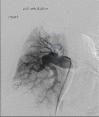

Bronchopulmonary arterial fistula consists of an abnormal connection between the bronchus and the vascular tree and is a rare but serious complication associated with a variety of lung interventions. We present a case of a 61-year-old female with a history of metastatic breast cancer treated with lumpectomy and radiation 20 years prior, who was found to have a fistula between the right pulmonary artery and the right mainstem bronchus. Our patient was treated endovascularly with coil embolization in the setting of massive hemoptysis flooding the trachea, which was successful in controlling the acute bleed, although care was withdrawn in the following days following a discussion with the family given the presence of advanced metastatic disease. This case illustrates the use of endovascular techniques to treat an actively bleeding bronchopulmonary arterial fistulae, including a review of the existing literature regarding the optimal endovascular management strategy. Although our patient did not achieve the best outcome, endovascular intervention with stent-placement or embolization can serve to temporarily halt blood flow through the fistula, stabilizing the patient and allowing for more radical therapy after improvement.